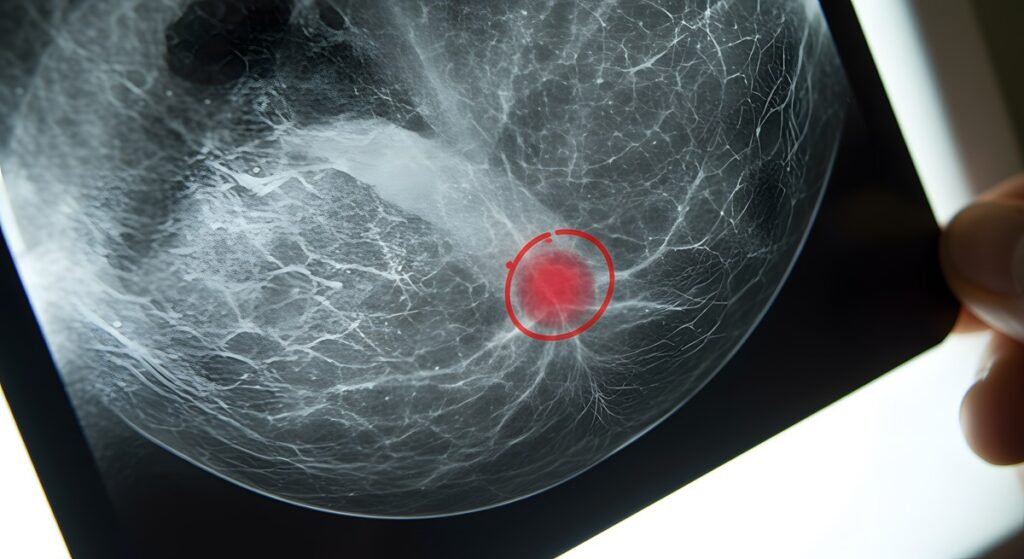

Quando falamos em “mamas densas”, significa que existe uma proporção maior de tecido fibroglandular (glandular e fibroso) em comparação ao tecido adiposo. É como se sua mama tivesse mais “estrutura” e menos gordura. Na mamografia, o tecido fibroglandular aparece branco, enquanto a gordura aparece escura (cinza).

A densidade mamária é identificada durante a realização da mamografia. O radiologista avalia cuidadosamente a quantidade de tecido fibroglandular presente nas imagens e classifica a mama em uma das quatro categorias estabelecidas pelo Colégio Americano de Radiologia (ACR):

Mulheres nas categorias C e D são consideradas como portadoras de mamas densas.

- Aumento do Risco: Mulheres com mamas heterogeneamente ou extremamente densas (categorias C e D) têm um risco leve a moderadamente maior de desenvolver câncer de mama em comparação com mulheres com mamas adiposas. A razão exata ainda é estudada, mas acredita-se que o próprio ambiente do tecido denso possa favorecer o desenvolvimento de células anormais.

- O “Efeito de Mascaramento”: Este é o desafio mais conhecido. Como o tecido denso e um possível nódulo aparecem brancos na mamografia, a densidade pode funcionar como uma “camuflagem”, escondendo lesões em estágios iniciais. É como tentar encontrar um urso polar em uma tempestade de neve: não é impossível, mas é mais difícil.